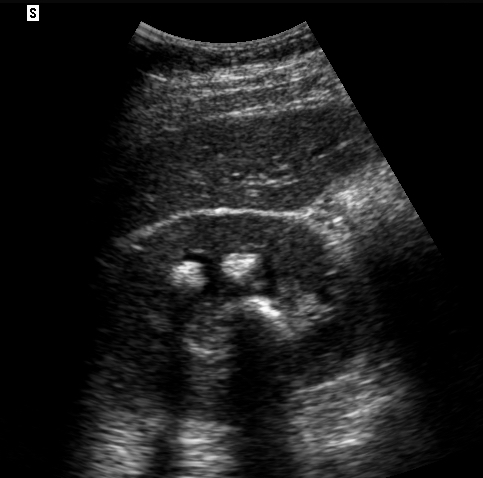

- Figures 5 and 6. Renal stones (arrows) with shadowing

- Stones at the ureteropelvic junction - look for a bright object that casts a shadow at the hilum as the renal pelvis narrows to form the ureter.